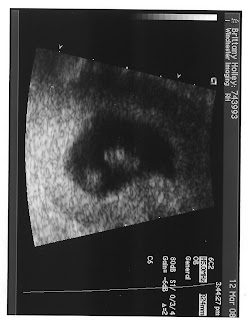

I am currently 34 weeks pregnant and wishing it would end already! I love feeling the kicks and movements of this little guy but I want to hold him!!! Scott and I went to a Birth class, Scott did NOT pass out watching the live birth video, which gives me hope that they will not need a spatula to scrape him off the floor, but no guarentee yet! The most current picture of the belly is me in action at the sink! We have been bad at documenting belly growth... but this one was in the beginning of August.

We have also been preparing for our little blessing Ethan Edward to arrive! We rearranged the house, moving our office into the 3rd smaller room and setting up the Nursery in what used to be the office. It is very cute and I will post a picture once I get the camera from Scott. Let the nesting begin! There are still some small cleaning projects to do, lots of baby stuff to buy, but we still have 6 weeks plus or minus 2, to get ready, but time is flying. The Kitties have no idea what is comming!